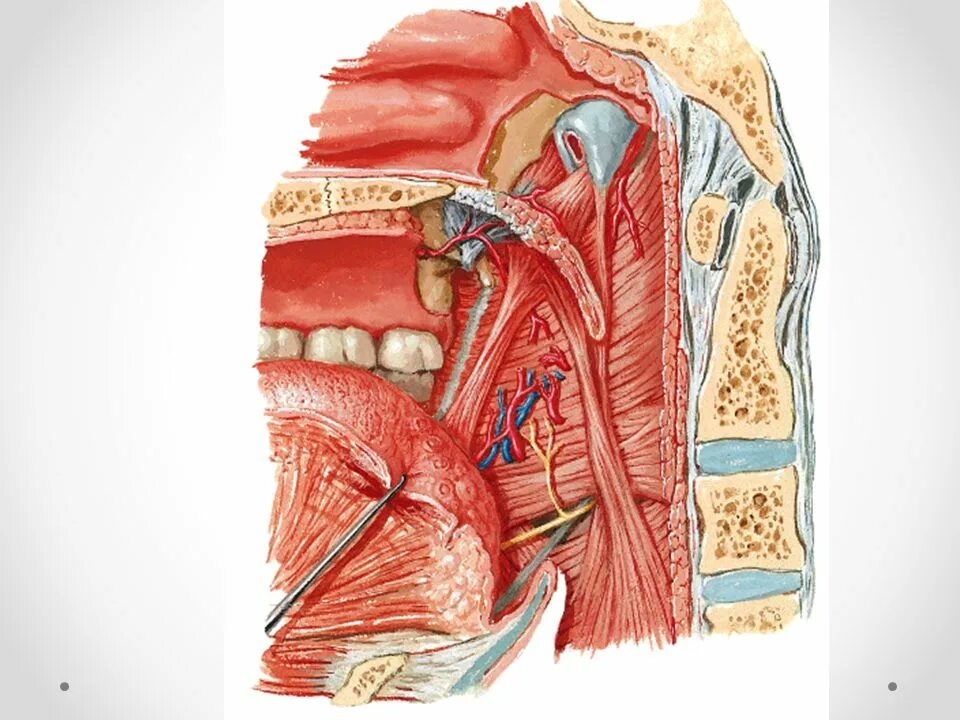

Tensor veli